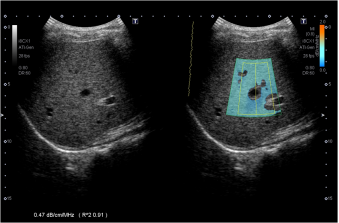

8.声衰减成像ATI(Attenuation imaging) --独有的技术

ATI通过智能测量衰减系数来量化衰减 dB/cm/MHz。

ATI对于脂肪变性和纤维化分期的声衰减值精准定量,结合SWE和超声造影技术,利于肝脏病变智能全面定量分析,更好的进行肝脏疾病的管理。